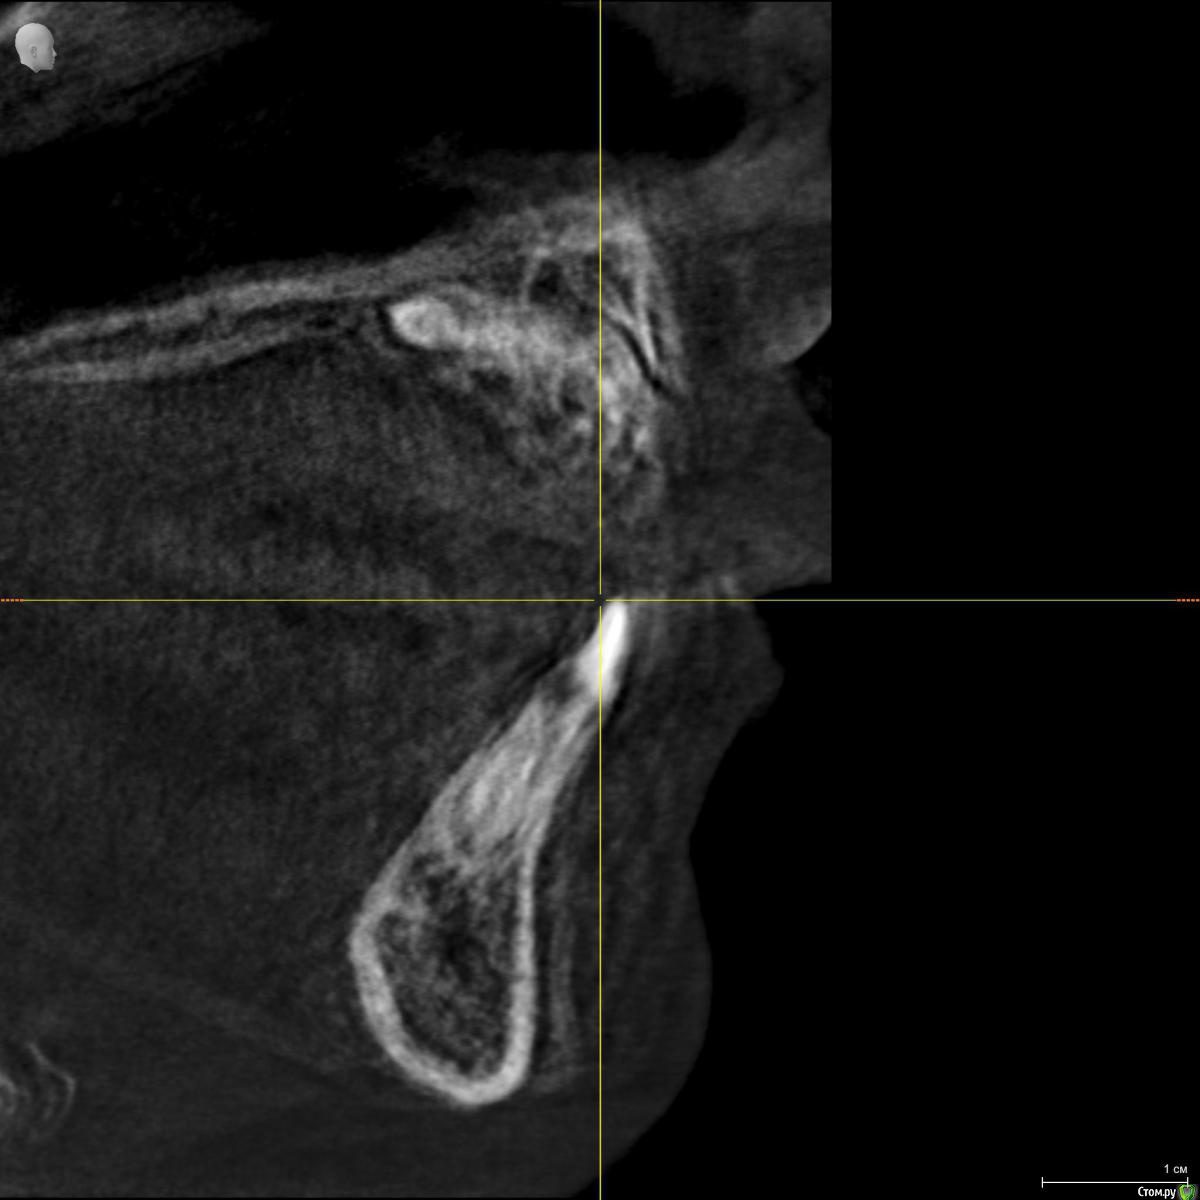

Ребенок 6 лет.

По теме интересует какие лишние зубы можно дождаться и удалить после прорезывания, какие требуют оперативного вмешательства, какие сроки, тот что на месте 11 не вниз корнем?

Были в 4 клиниках, случай не типичный, варианты лечения разные. От ничего не делать ждать, до резать удалять. Начинали с 2 сверхкомплектов, потом нашли еще два.